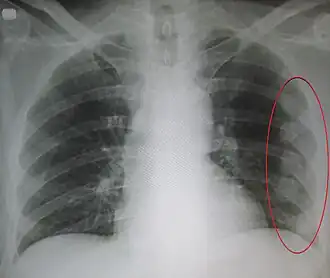

| Um raio-X mostrando múltiplas costelas quebradas do lado esquerdo da pessoa conforme marcado pela oval | |

A fratura na costela é a quebra de um dos ossos da costela.[1] Isto normalmente resulta em dor no peito que piora com a respiração. Hematomas podem ocorrer no local da quebra.[3] Quando várias costelas estão quebradas em vários lugares resulta em um tórax instável.[4] Complicações potenciais incluem um pneumotórax, contusão pulmonar e pneumonia.